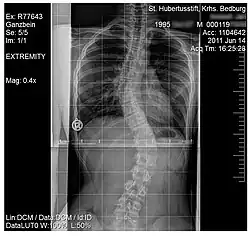

Scoliosis

.jpg)

Scoliosis, is a medical condition where a person's spine has several irregular curves that are located between the neck and the pelvis.[8] Symptoms of scoliosis in mild cases usually exhibit abnormal posture, back pain, tingling or numbness in the legs and in worse cases can exhibit breathing problems, fatigue, permanent deformities and in rare cases heart problems.[8]